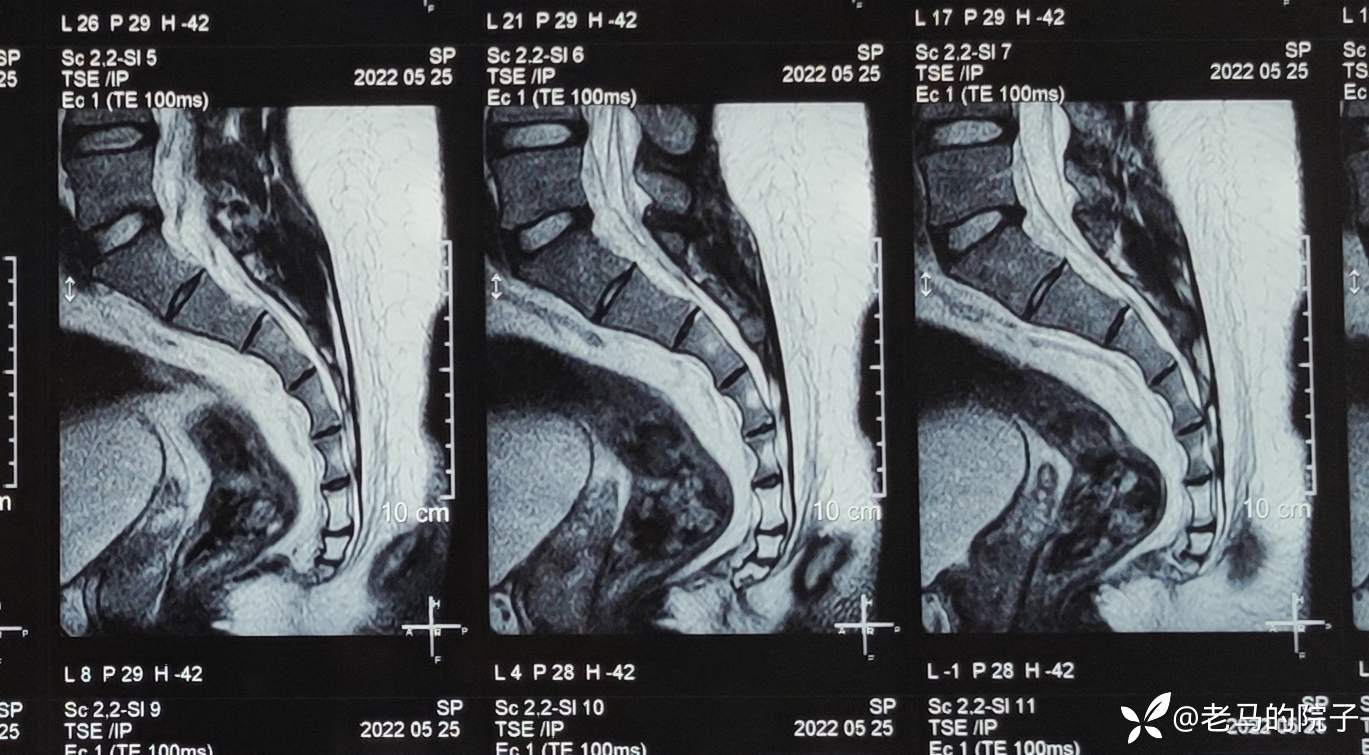

入院后查MRI见下图1、图2、图3

图1

图2

图3

MR影像报告单见下图

骶尾部核磁脂肪层内异常信号,未见与骶尾部神经有关系,未见骨质破坏